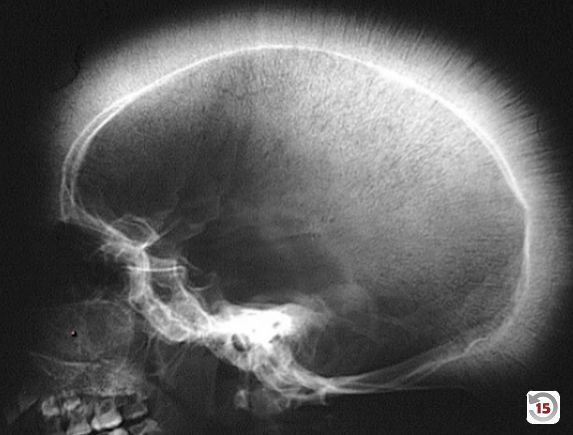

- Clinical Features: Massive hepatosplenomegaly from extramedullary hematopoiesis, “crewcut” appearance on skull x-ray, and “chipmunk” facies due to bone marrow expansion.

- Skull x-ray: Hair-on-end (also known as “crew cut”) sign, caused by excessive expansion of the bone marrow to compensate for the destruction of red blood cells